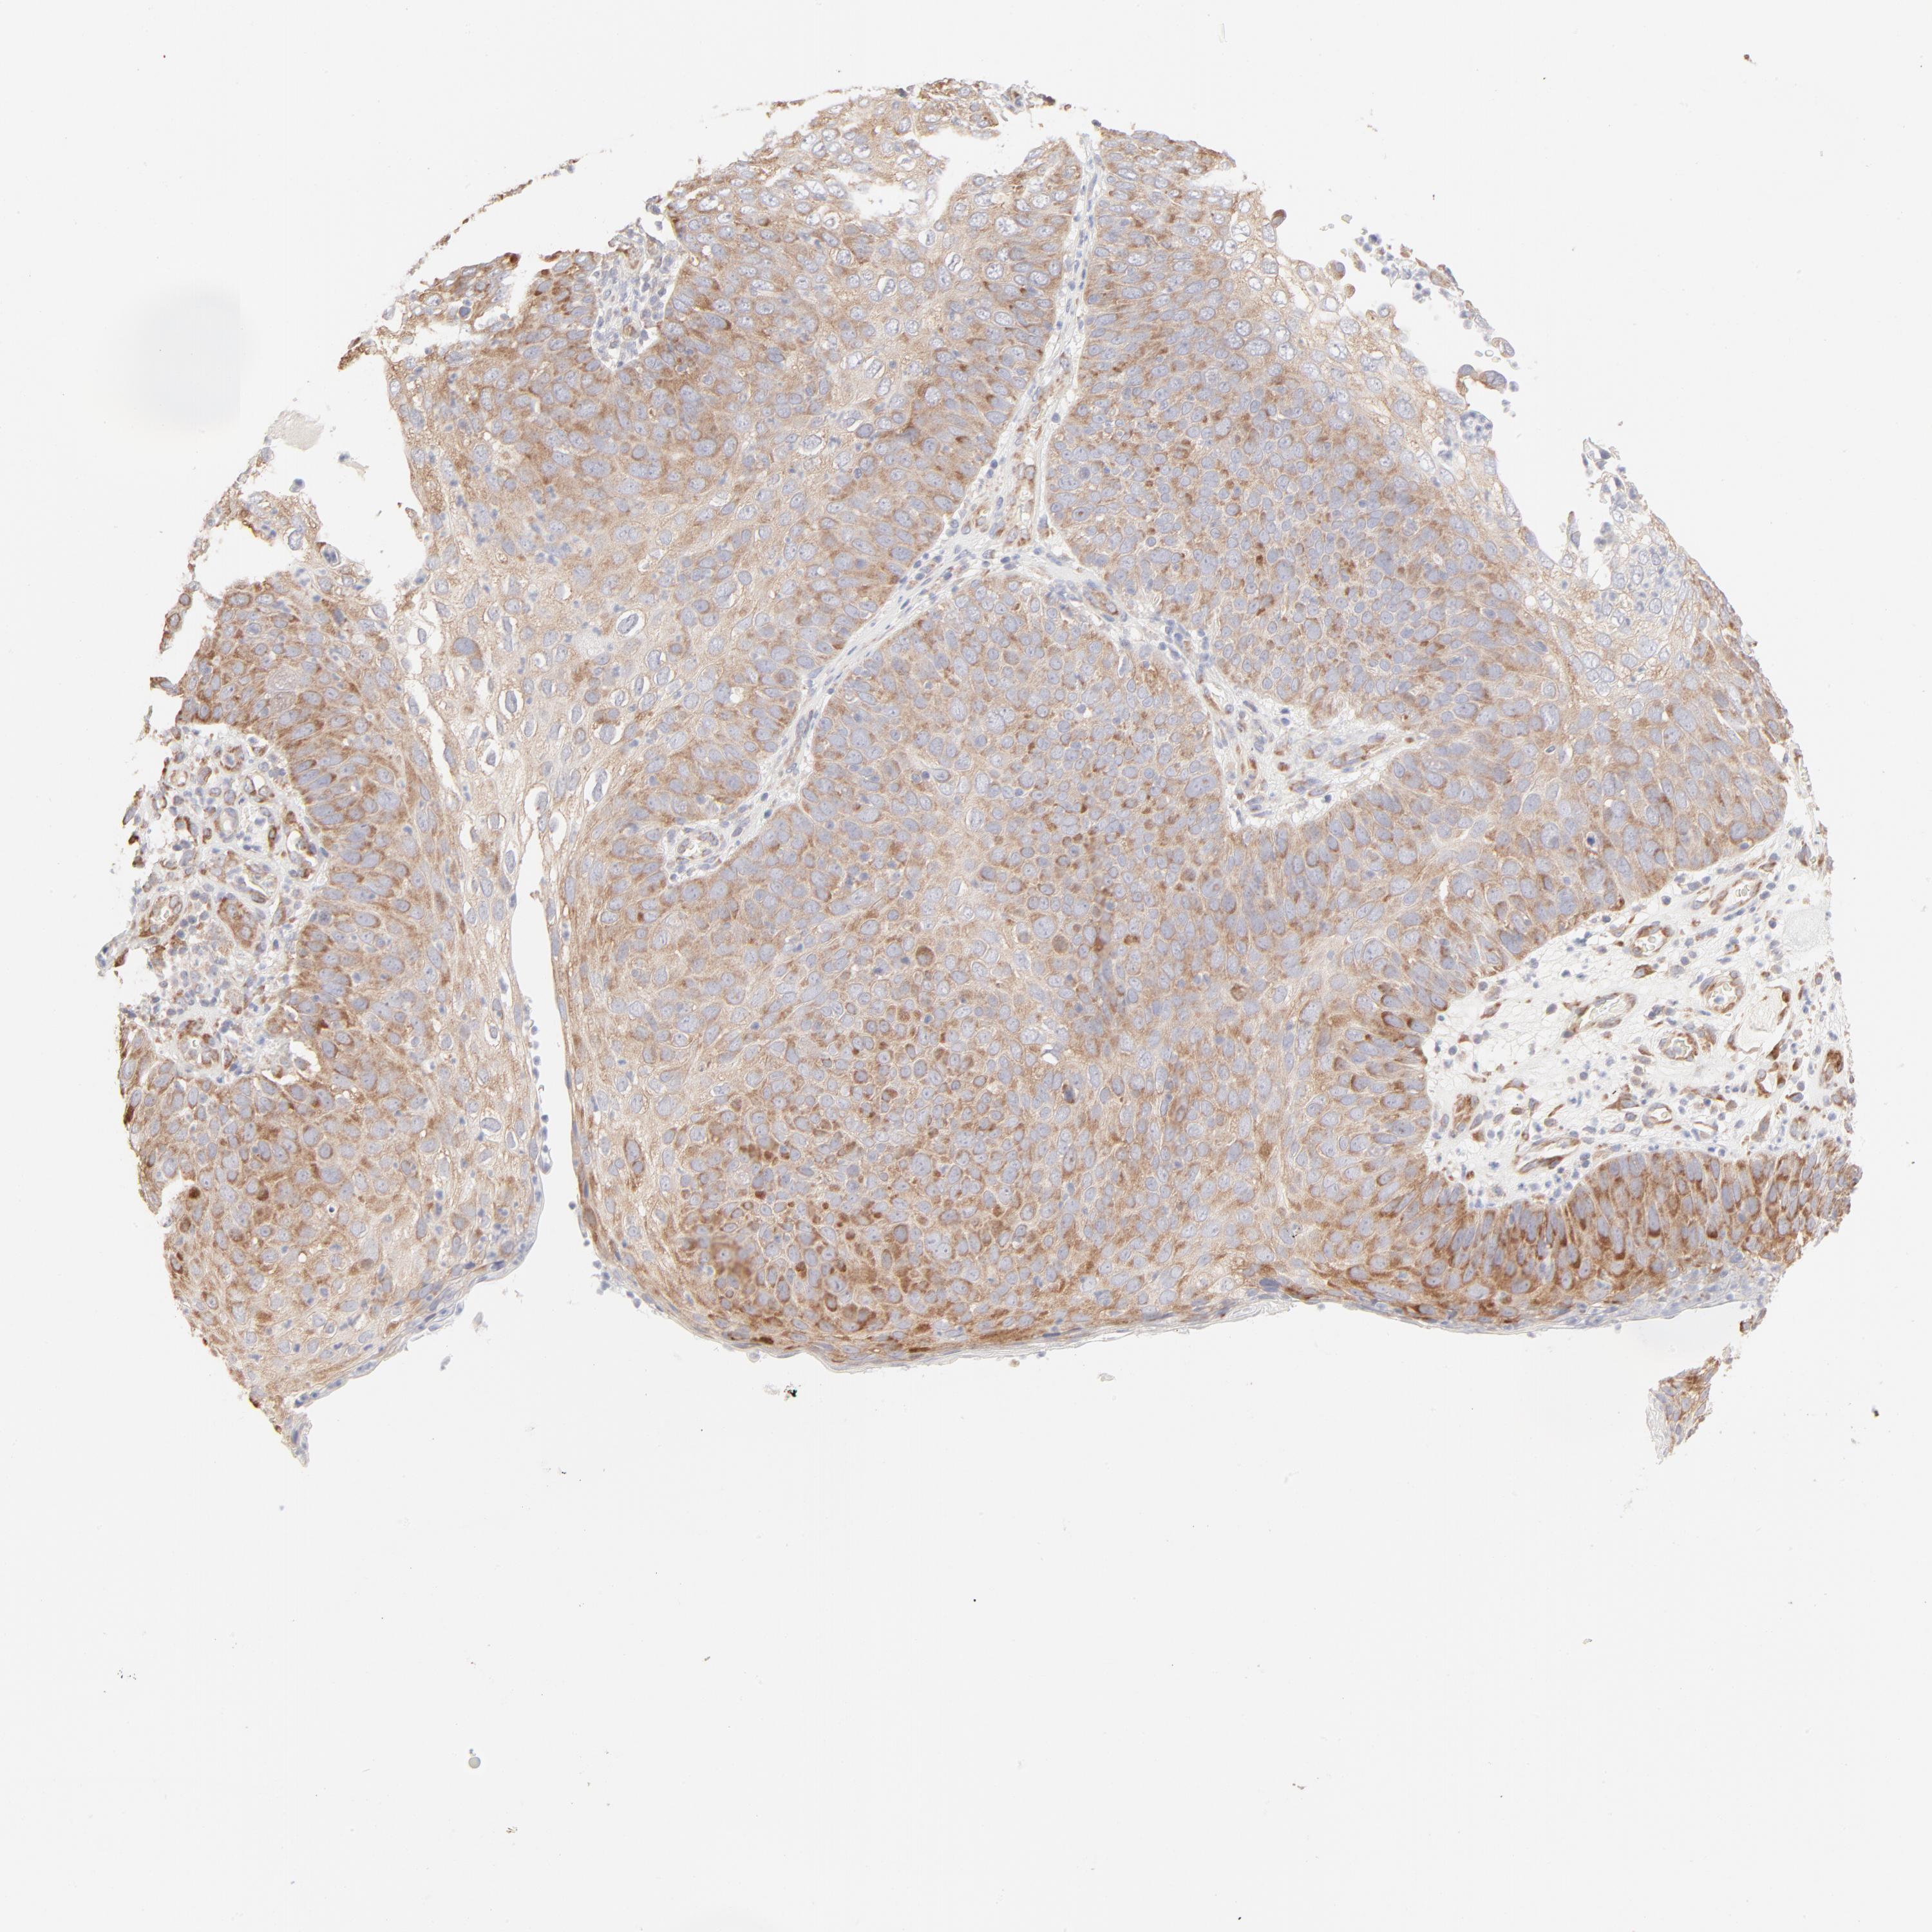

CANCER SKIN CANCER Show tissue menu

Basal cell and squamous cell cancer

SKIN CANCER - Protein expressioni

A mouse-over function shows sample information and annotation data. Click on an image to view it in a full screen mode. Samples can be filtered based on level of antibody staining by selecting one or several of the following categories: high, medium, low and not detected. The assay and annotation is described here.

Antibody stainingi

Antibody staining in the annotated cell types in the current human tissue is reported as not detected, low, medium, or high, based on conventional immunohistochemistry profiling in selected tissues. This score is based on the combination of the staining intensity and fraction of stained cells.

Each image is clickable and will lead to virtual microscopy that enables deeper exploration of all samples and also displays staining intensity scores, fraction scores and subcellular localization as well as patient and tissue information for each sample.

Antibody HPA003371

Staining

High

Intensity

Strong

Quantity

>75%

Location

Nuclear

Cytoplasmic/membranous

Cytoplasmic/membranous,nuclear

Squamous cell carcinoma, NOS

Basal cell carcinoma